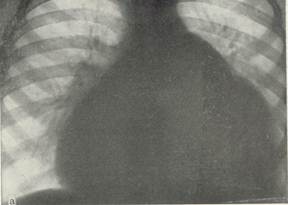

Дівчинка 11 міс. Cкарги батьків на швидку її втомлюваність при годуванні, раптове посилення ціанозу та задухи при плачі. Об¢єктивно: Стан середньої важкості, відставання в фізичному розвитку. В спокої – помірно виражений ціаноз шкірних покривів, слизові з фіолетовим відтінком, ціаноз посилюється при плачі дитини. Під час огляду на фоні неспокою значно посилився ціаноз, почастішало дихання, дитина стала вкрай неспокійною, на руках у матері з притиснутими до живота ніжками трохи заспокоїлась. Дихання 64 на хв, над легенями ясний перкуторний звук, жорстке дихання Пульс 150 за хв. Межі серця: розширені вправо. Над всією поверхнею грудної клітки вислуховується грубий систолічний шум із максимальною звучністю в 2-му міжребер'ї зліва від грудини, другий тон ослаблений над легеневою артерією. Загальний аналіз крові: Hb -200 г/л; еритроцити – 6,0 Т/л, КП – 0,95; нейтрофіли: паличкоядерні -5%, сегментоядерні -39%; еозинофіли-3%; лімфоцити-50%; моноцити - 3%; ШЗЕ - 4 мм/год. Рентгенологічне обстеження ОГК: див. рис.

Дівчинка 11 міс. Cкарги батьків на швидку її втомлюваність при годуванні, раптове посилення ціанозу та задухи при плачі. Об¢єктивно: Стан середньої важкості, відставання в фізичному розвитку. В спокої – помірно виражений ціаноз шкірних покривів, слизові з фіолетовим відтінком, ціаноз посилюється при плачі дитини. Під час огляду на фоні неспокою значно посилився ціаноз, почастішало дихання, дитина стала вкрай неспокійною, на руках у матері з притиснутими до живота ніжками трохи заспокоїлась. Дихання 64 на хв, над легенями ясний перкуторний звук, жорстке дихання Пульс 150 за хв. Межі серця: розширені вправо. Над всією поверхнею грудної клітки вислуховується грубий систолічний шум із максимальною звучністю в 2-му міжребер'ї зліва від грудини, другий тон ослаблений над легеневою артерією. Загальний аналіз крові: Hb -200 г/л; еритроцити – 6,0 Т/л, КП – 0,95; нейтрофіли: паличкоядерні -5%, сегментоядерні -39%; еозинофіли-3%; лімфоцити-50%; моноцити - 3%; ШЗЕ - 4 мм/год. Рентгенологічне обстеження ОГК: див. рис.

1. Який попередній діагноз? Яке ускладнення розвинулось у дитини? Опишіть патологічні зміни в аналізі крові, на ЕКГ, ЕхоКГ та на рентгенограмі.